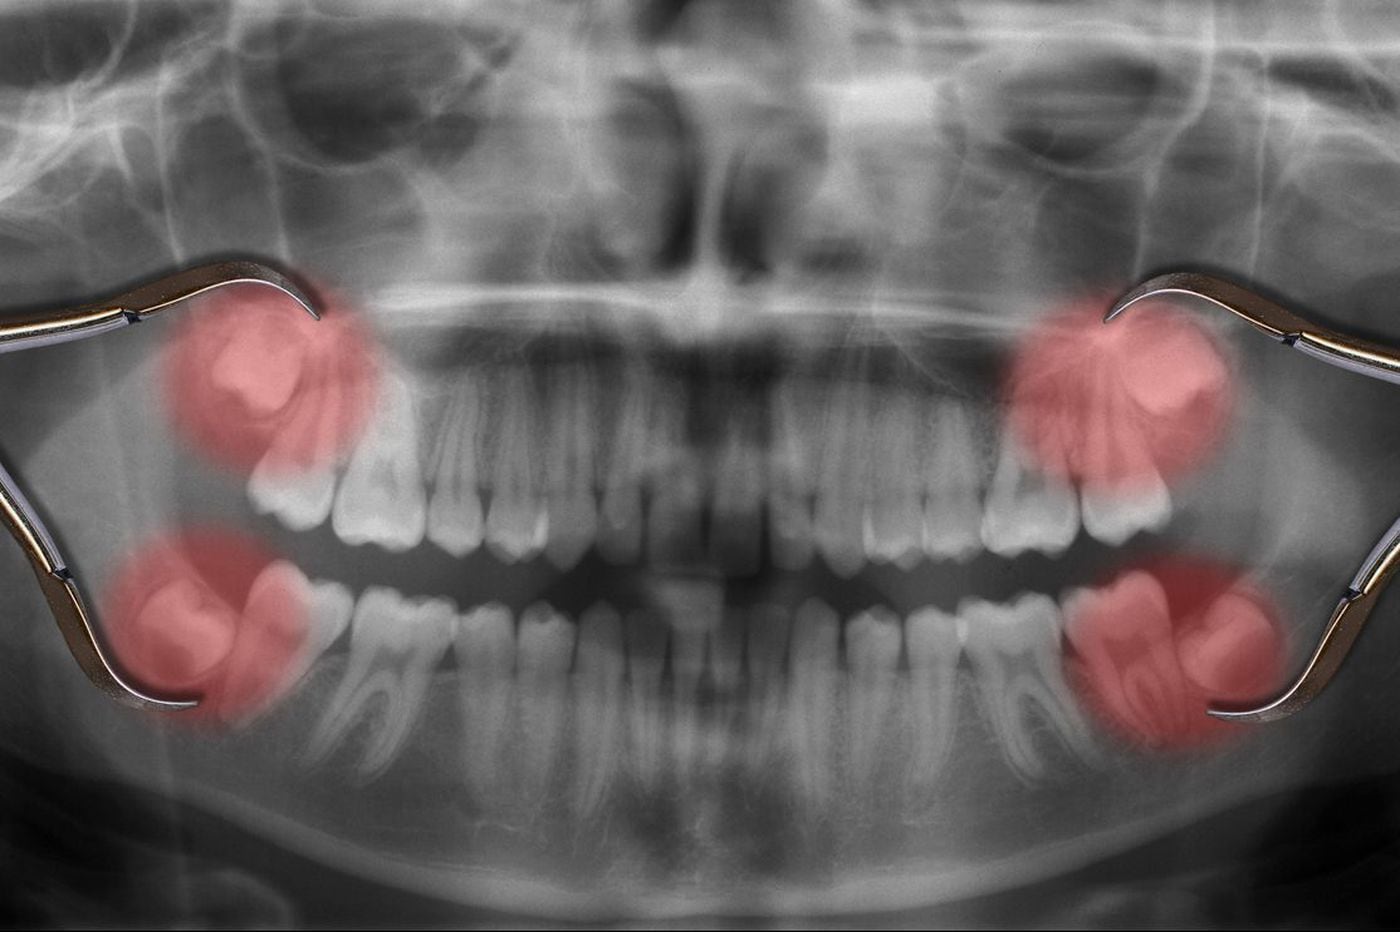

Get How Long Is Wisdom Teeth Recovery Pics. Recovery from wisdom teeth surgery takes about three days, but can take up to a week or more. The dental surgeon will usually remove the stitches after about 1 week.

Recovery from wisdom teeth surgery takes about three days, but can take up to a week or more. How to survive wisdom teeth surgery: Most wisdom teeth are removed within a couple of minutes and the operation is relatively quick.